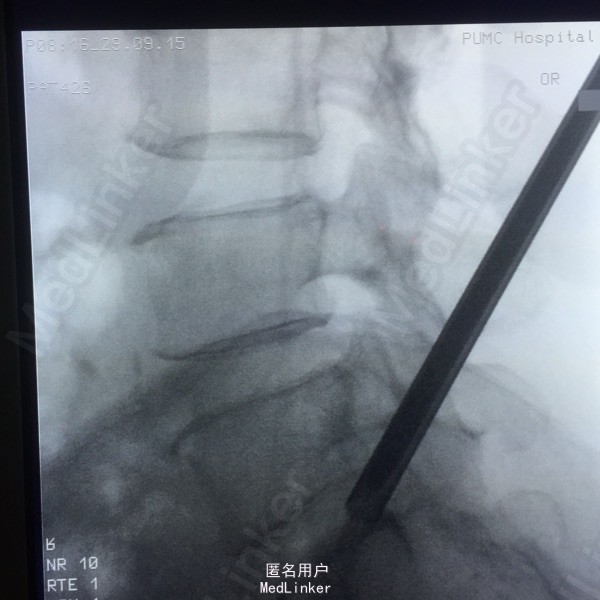

65岁女性,右下肢放射性疼痛2年半,保守治疗效果不佳 2年前曾行C5-6的ACDF术。

L5-S1左侧棘旁压痛(+),右小腿外侧针刺觉稍弱,右侧跟腱反射稍弱。 腰椎CT提示L5-S1间盘突出,偏右侧。 腰椎X线片提示髂嵴偏高,L5横突肥大。

L5-S1椎间盘突出 C5-6 ACDF术后 拟行椎间孔镜手术

因为穿刺通道比较狭小,进入椎间盘时偏杨氏,采用由内而外的方式减压神经根,用镜下弹性弯钳较好完成了神经根减压。